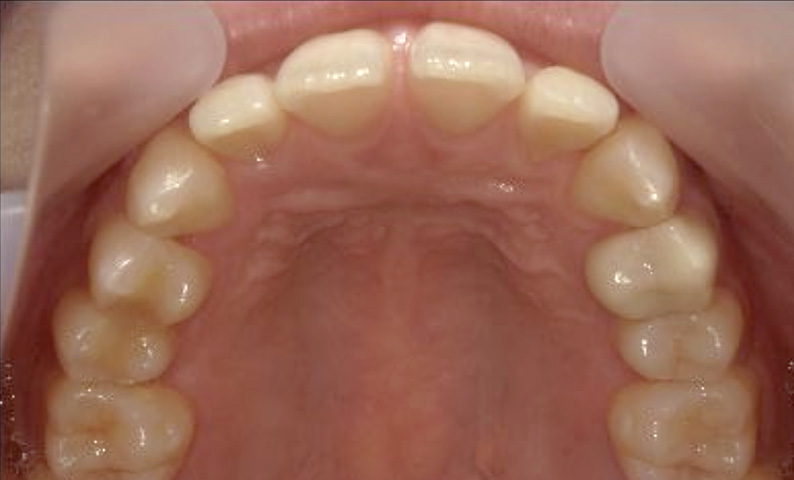

症例_019 上下顎の部分矯正

治療期間:8ヶ月金額:48万円+税女性前歯のガタガタ

| Before | After |

|---|---|

|